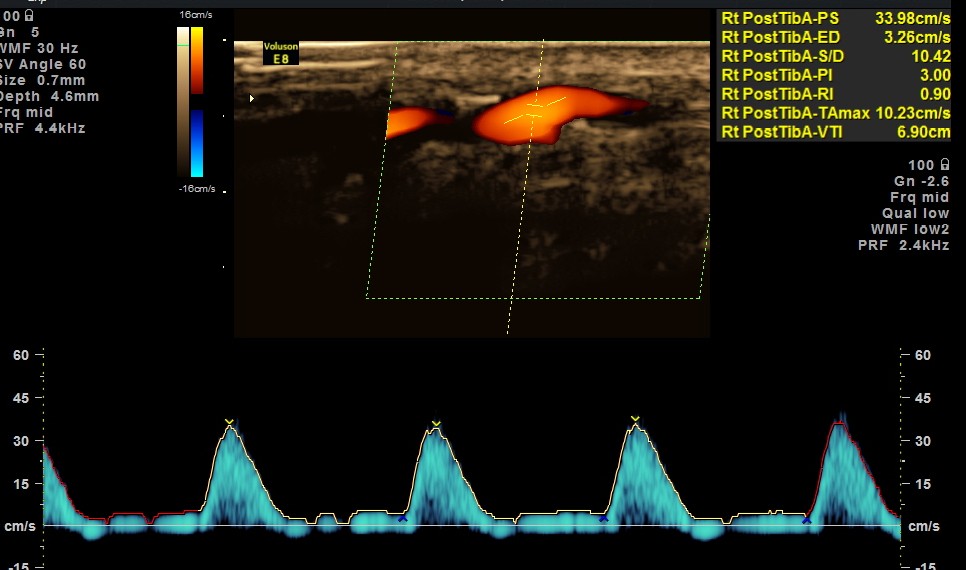

BOTH DORSALIS PEDIS ARTERIES SHOW LOSS OF ARTERIAL TONE AND MONOPHASIC FLOW.

EXTENSIVE ATHEROSCLEROTIC OBSTRUCTIVE DISEASE OF THE LOWER LIMB ARTERIES WAS SEEN WITH THE CHANGES IN THE RIGHT COMMON FEMORAL ARTERY BEING MORE THAN THE LEFT CFA.